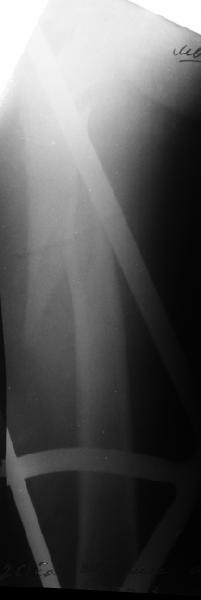

Второй случай тоже репозиция из малого доступа, больному 19 лет, множественные огнестрельные повреждениия конечностей, живота и черепа, правая конечность холодная, без пульсации. Ортопедический диагноз: огнестрельный перелом правого бедра. При срочной ангиографии повреждения сосудов не подтвердилось, конечность из-за ургентности состояния больного зафиксирована временным наружным фиксатором и больной оставлен на операционном столе для срочной лапаротомии хирургической службой.

Больной долго оставался нестабильным, только на 14 день удалось заменить на антеградный интромедуллярный штифт TFN (trochanteric femoral nail) SmithNephew. После неудачной попытки закрытой репозиции, несмотря на использование "joystick", проксимальный стержень от

наружного фиксатора, (перелом начал срастаться) репозицию провели из малого доступа, затем остальные этапы операции.

Случай был представлен из-за того, что больного оперировали после наружной фиксации и был риск инфекцирования через места проведения стержней (на снимках), прошло больше 3 месяцев, выписан из амбулаторной службы из-за отсутсвия надобности дальнейшего наблюдения.